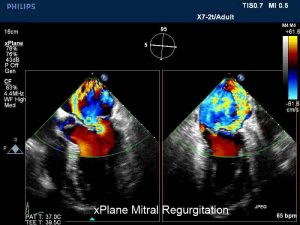

Centrul Medical Maycor e clinica de cardiologie din Galati care a investit intr-un ecocardiograf performant si anume in sistemul Philips iE33 xMatrix, care permite obtinerea de imagini 3D (tridimensional) si…

Ecografia cardiaca sau ecocardiografia, una dintre cele mai importante si utilizate metode de imagistica, este o investigatie care dureaza aproximativ 15-20 de minute, prin care se vizualizeaza inima cu ajutorul…